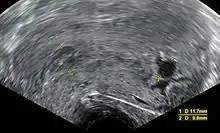

Ultrasound criteria

A review article in The New England Journal of Medicine based on a consensus meeting of the Society of Radiologists in Ultrasound in America (SRU) has suggested that miscarriage should be diagnosed only if any of the following criteria are met upon ultrasonography visualization:[92]

Miscarriaged diagnosed Miscarriage suspected References

Crown-rump length of at least 7 mm and no heartbeat. Crown–rump length of less than 7 mm and no heartbeat. [92][93]

Mean gestational sac diameter of at least 25 mm and no embryo. Mean gestational sac diameter of 16–24 mm and no embryo. [92][93]

Absence of embryo with heartbeat at least 2 weeks after an ultrasound scan that showed a gestational sac without a yolk sac. Absence of embryo with heartbeat 7–13 days after an ultrasound scan that showed a gestational sac without a yolk sac. [92][93]

Absence of embryo with heartbeat at least 11 days after an ultrasound scan that showed a gestational sac with a yolk sac. Absence of embryo with heartbeat 7–10 days after a scan that showed a gestational sac with a yolk sac. [92][93]

Absence of embryo at least 6 weeks after last menstrual period. [92][93]

Amniotic sac seen adjacent to yolk sac, and with no visible embryo. [92][93]

Yolk sac of more than 7 mm. [92][93]

Small gestational sac compared to embryo size (less than 5 mm difference between mean sac diameter and crown–rump length). [92][93]